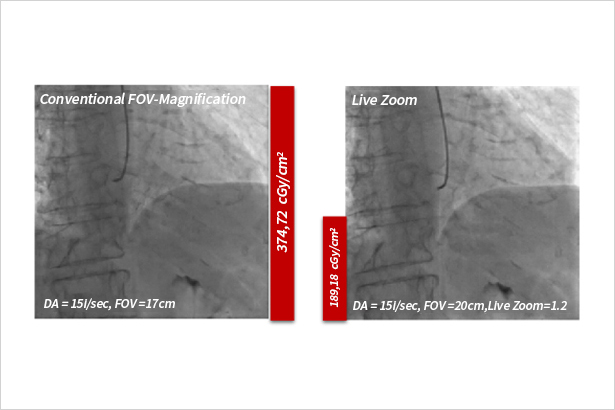

針對動態透視圖像進行放大顯示,且不會造成劑量增高